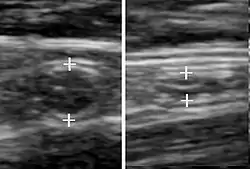

Ultrasound

Ultrasound image of acute appendicitis

Abdominal ultrasonography, preferably with doppler sonography, is useful to detect appendicitis, especially in children. Ultrasound can show the free fluid collection in the right iliac fossa, along with a visible appendix with increased blood flow when using color Doppler, and noncompressibility of the appendix, as it is essentially walled-off abscess. Other secondary sonographic signs of acute appendicitis include the presence of echogenic mesenteric fat surrounding the appendix and the acoustic shadowing of an appendicolith.[45] In some cases (approximately 5%),[46] ultrasonography of the iliac fossa does not reveal any abnormalities despite the presence of appendicitis. This false-negative finding is especially true of early appendicitis before the appendix has become significantly distended. Also, false-negative findings are more common in adults where larger amounts of fat and bowel gas make visualizing the appendix technically difficult. Despite these limitations, sonographic imaging with experienced hands can often distinguish between appendicitis and other diseases with similar symptoms. Some of these conditions include inflammation of lymph nodes near the appendix or pain originating from other pelvic organs such as the ovaries or Fallopian tubes. Ultrasounds may be either done by the radiology department or by the emergency physician.[47]